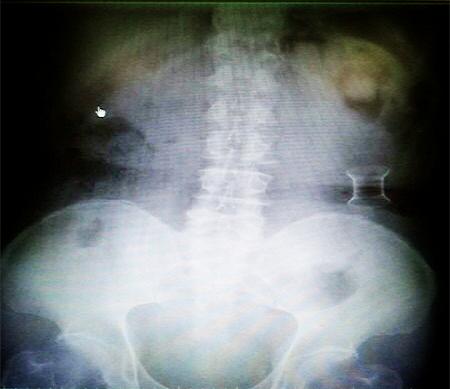

受試患者在結腸端端吻合術中,使用我司新研制產(chǎn)品達到了理想的預期效果。患者術后7天、14X光片顯影,可降解腸道支架均能按研制設計的預期時間節(jié)點保持應有強度,術后21X光片顯示可降解腸道支架已完全破碎,并排出體外。在整個試驗過程中,病患無任何不良反映,耐受良好。